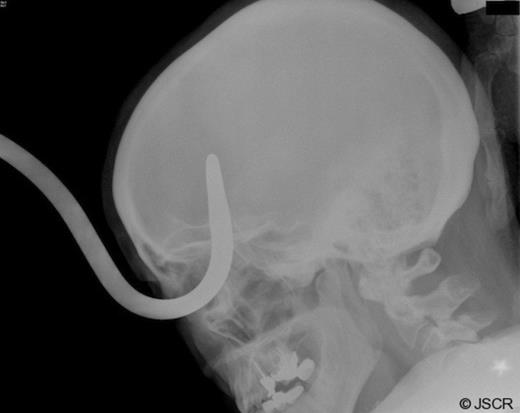

The patient was a 52 year old female who presented to the trauma bay of the University of Tennessee Medical Center-Knoxville via helicopter after suffering a fall. The patient admitted to falling onto a Sheppard-hook planter device while gardening. She denied any loss of consciousness, having dialed 911, for emergency services, herself after pulling the Sheppard-hook out of the ground and carrying it into her home. She presented with a Glascow Coma Scale score of 15, hemodynamically stable and had no other injuries. Her right eye had significant edema and could not be examined; however, the hook appeared to enter the orbit beneath the inferior eyelid, below the globe and through the roof of the orbital fossa (Figure 1).

After obtaining a four view skull series x-ray (Figure 2), it became evident the object traveled through the right orbital fossa superiorly, with the tip projecting over the medial right frontal lobe anterior to the pituitary, fracturing the posterior supero-medial orbital wall. Secondary to the size of the object, and with the assistance of emergency medical services and the fire department, the patient was taken outside to the ambulance bay where a plasma saw was utilized to separate the hook from the stanchion post in preparation for removal (Figure 3).